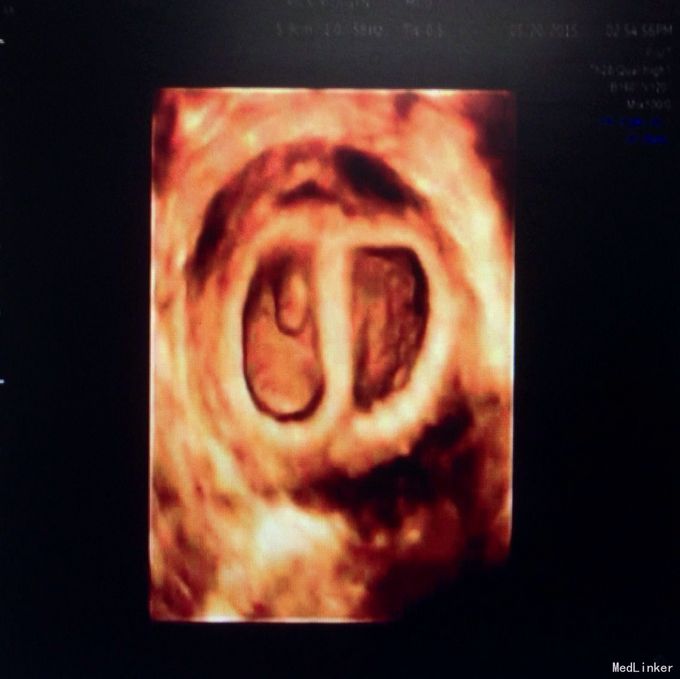

主诉:ET术后27天,呕吐1周 现病史:患者平素月经规律,5/28,27天前因“继发不孕”于我院行ET术,移植冻胚2个,1周前出现恶心、呕吐,呕吐呈喷射性,呕吐物为胃内容物,有胃部烧灼感,进食即吐,未予特殊治疗,门诊收入院。

体检:生命体征正常,无压痛及反跳痛,肝脾肋下未及,肾区叩痛(-),移动性浊音(-),双下肢无浮肿,未行内诊。 辅助检查:B超及生化相关检查如图

入院诊断:早孕,ET术后,妊娠剧吐 诊疗经过:入院后予营养补液支持治疗,达芙通口服黄体酮注射保胎治疗,复查血电解质尿常规正常后出院。